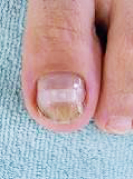

爪の切り過ぎによる巻き爪

矯正前